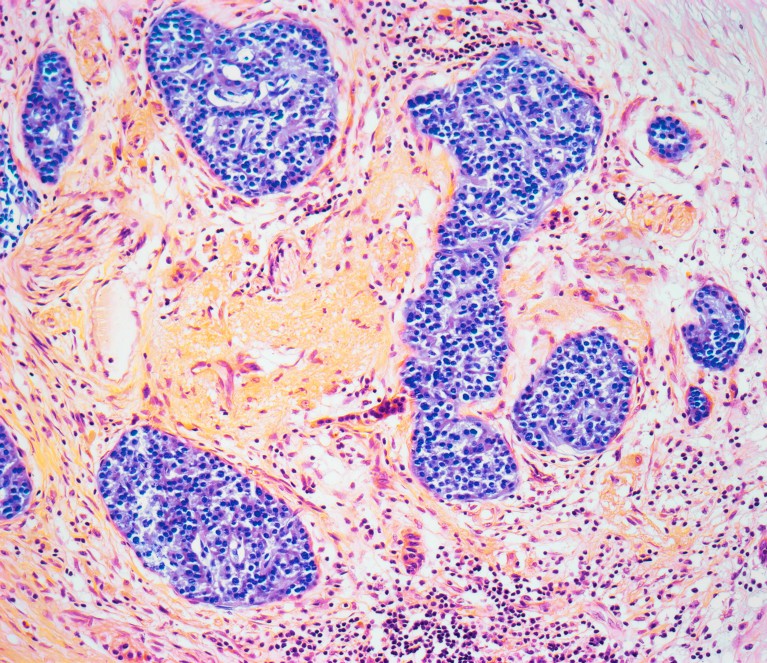

The condition called pancreatitis causes inflammation of the pancreatic tissue (pictured). Credit: Steve Gschmeissner/Science Photo Library